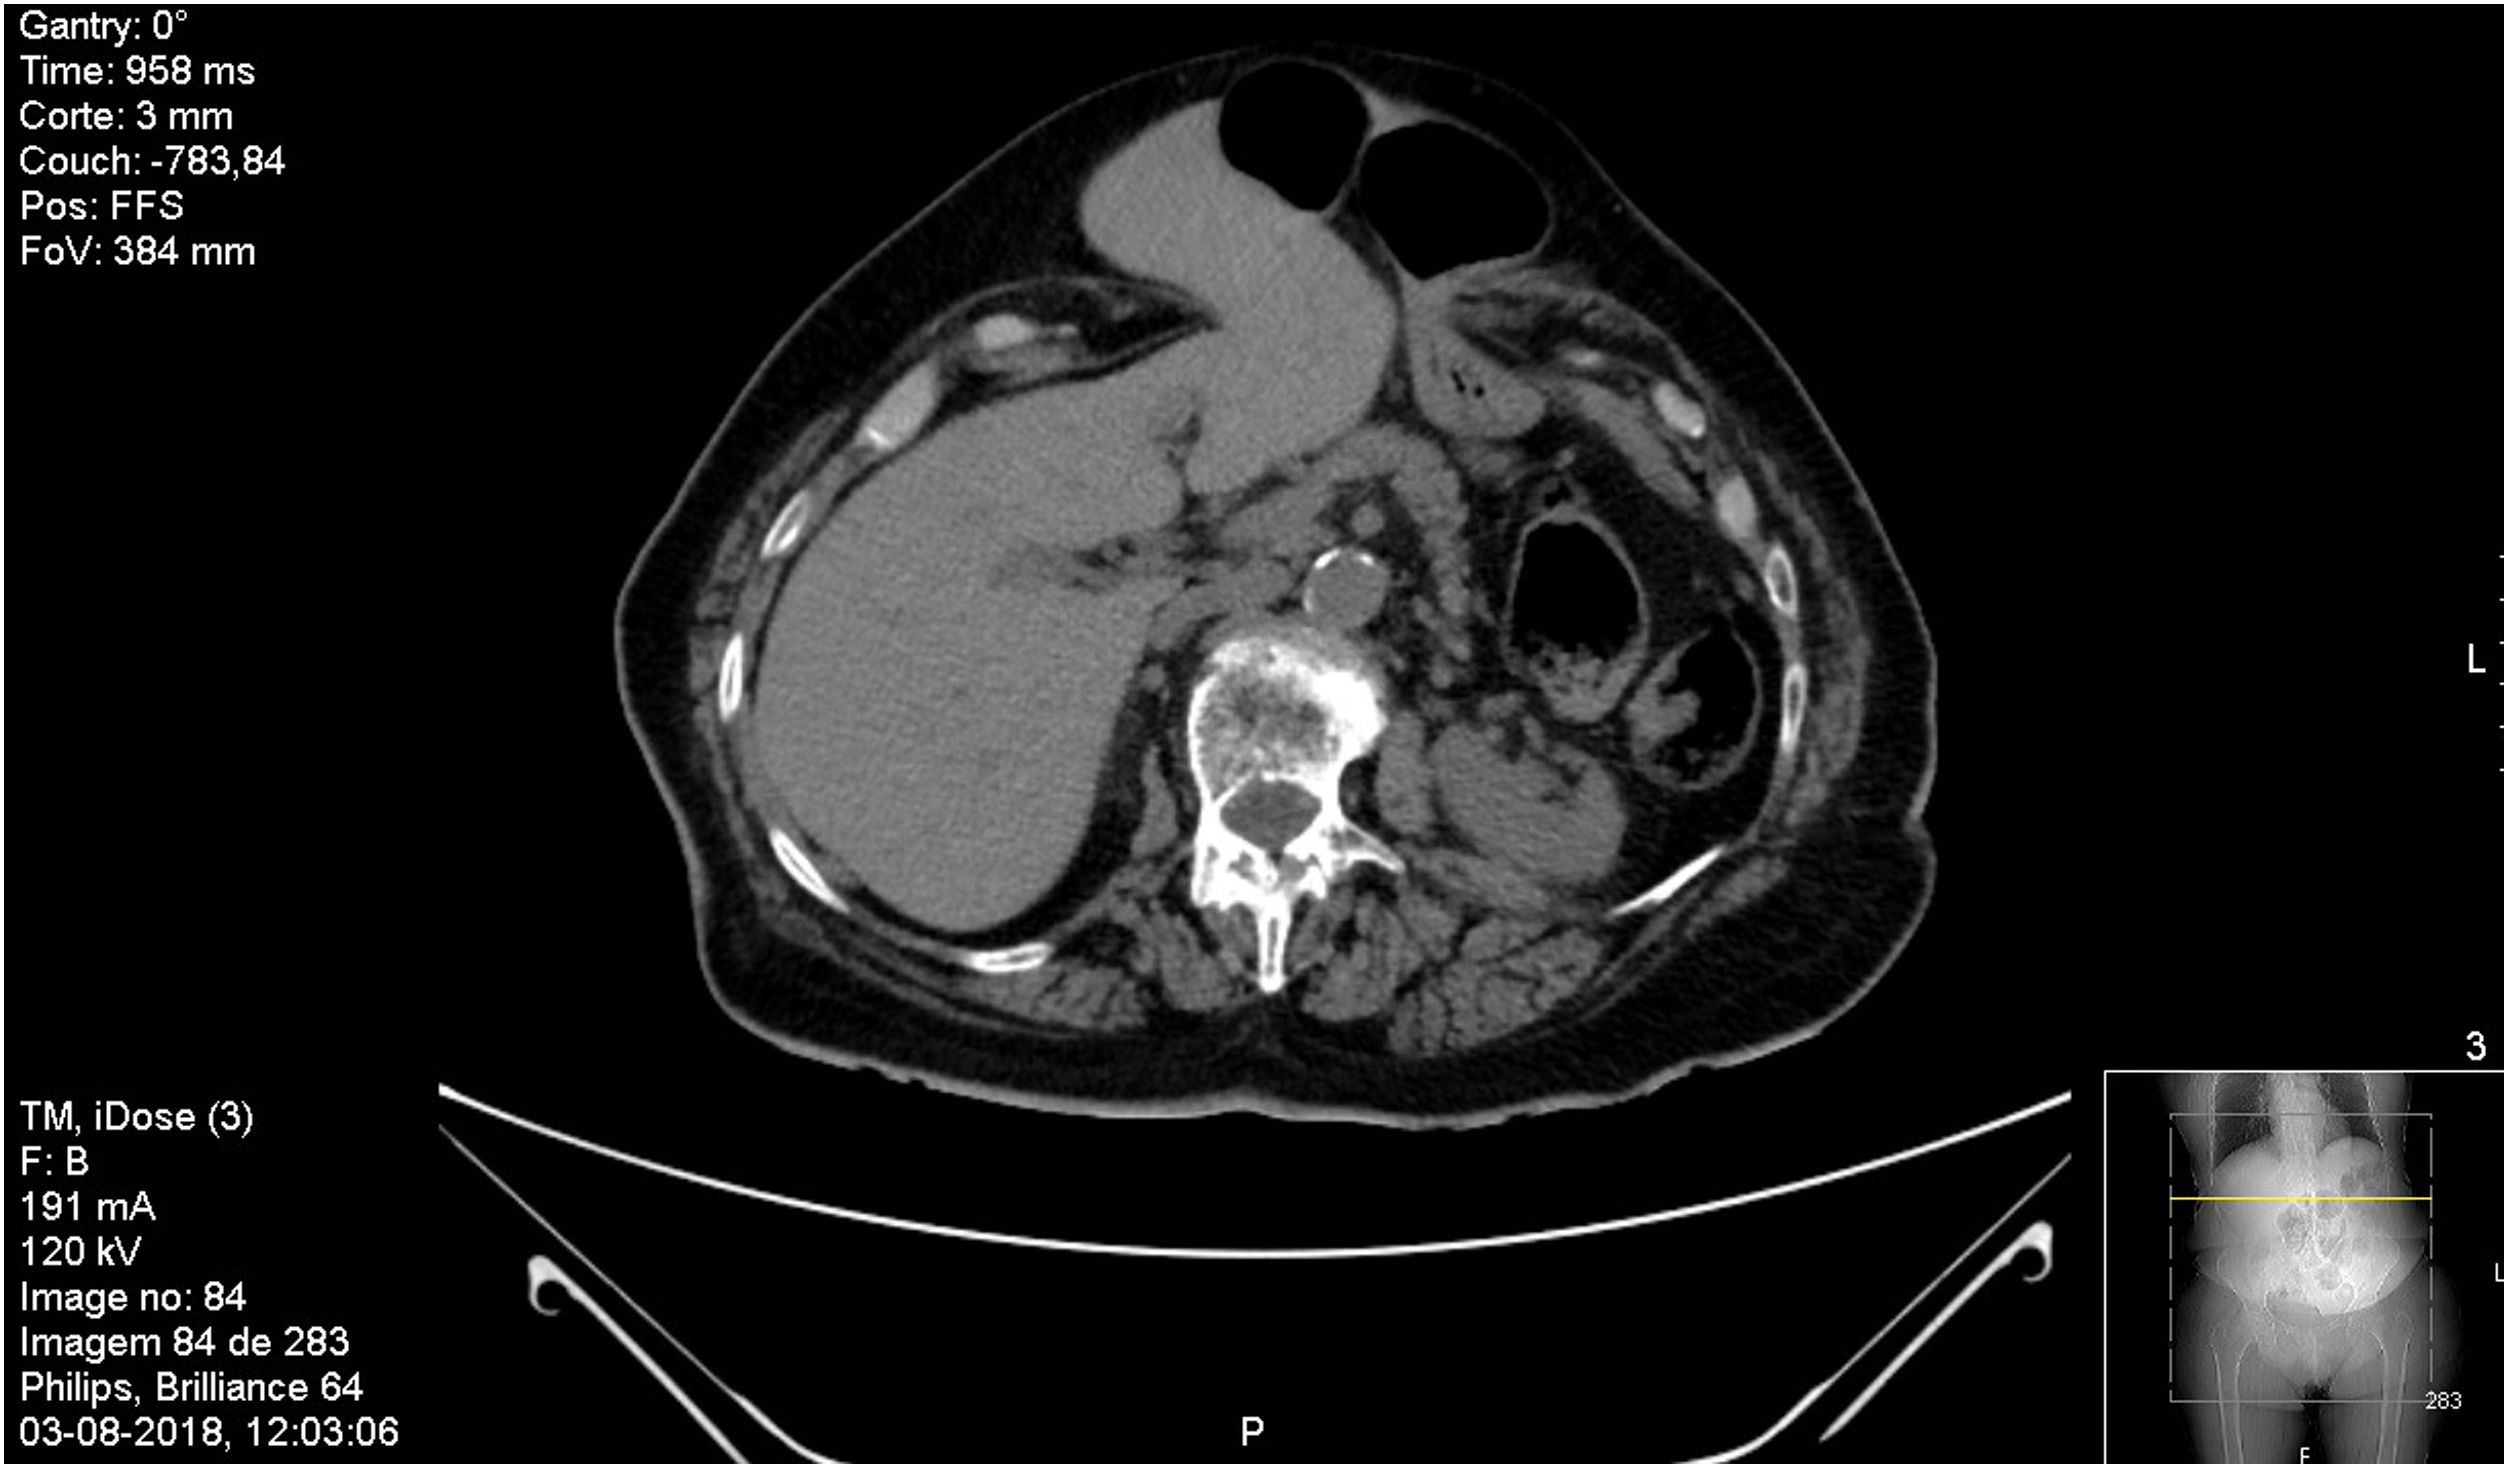

The protrusion of the liver lobe through an incisional hernia is a rare finding with very few cases reported in the literature. An 82-year-old woman underwent Hartmann's operation due to sigmoid adenocarcinoma. Three years later she was submitted to correction of a paracolostomy hernia with placement of prosthesis. The postoperative was complicated with dehiscence of abdominal suture and recurrent infections. The patient developed an incisional hernia at the level of the white line, the hernia sac containing part of the left lobe of the liver as well as the gastric antrum and part of the transverse colon (Figs. 1 and 2).